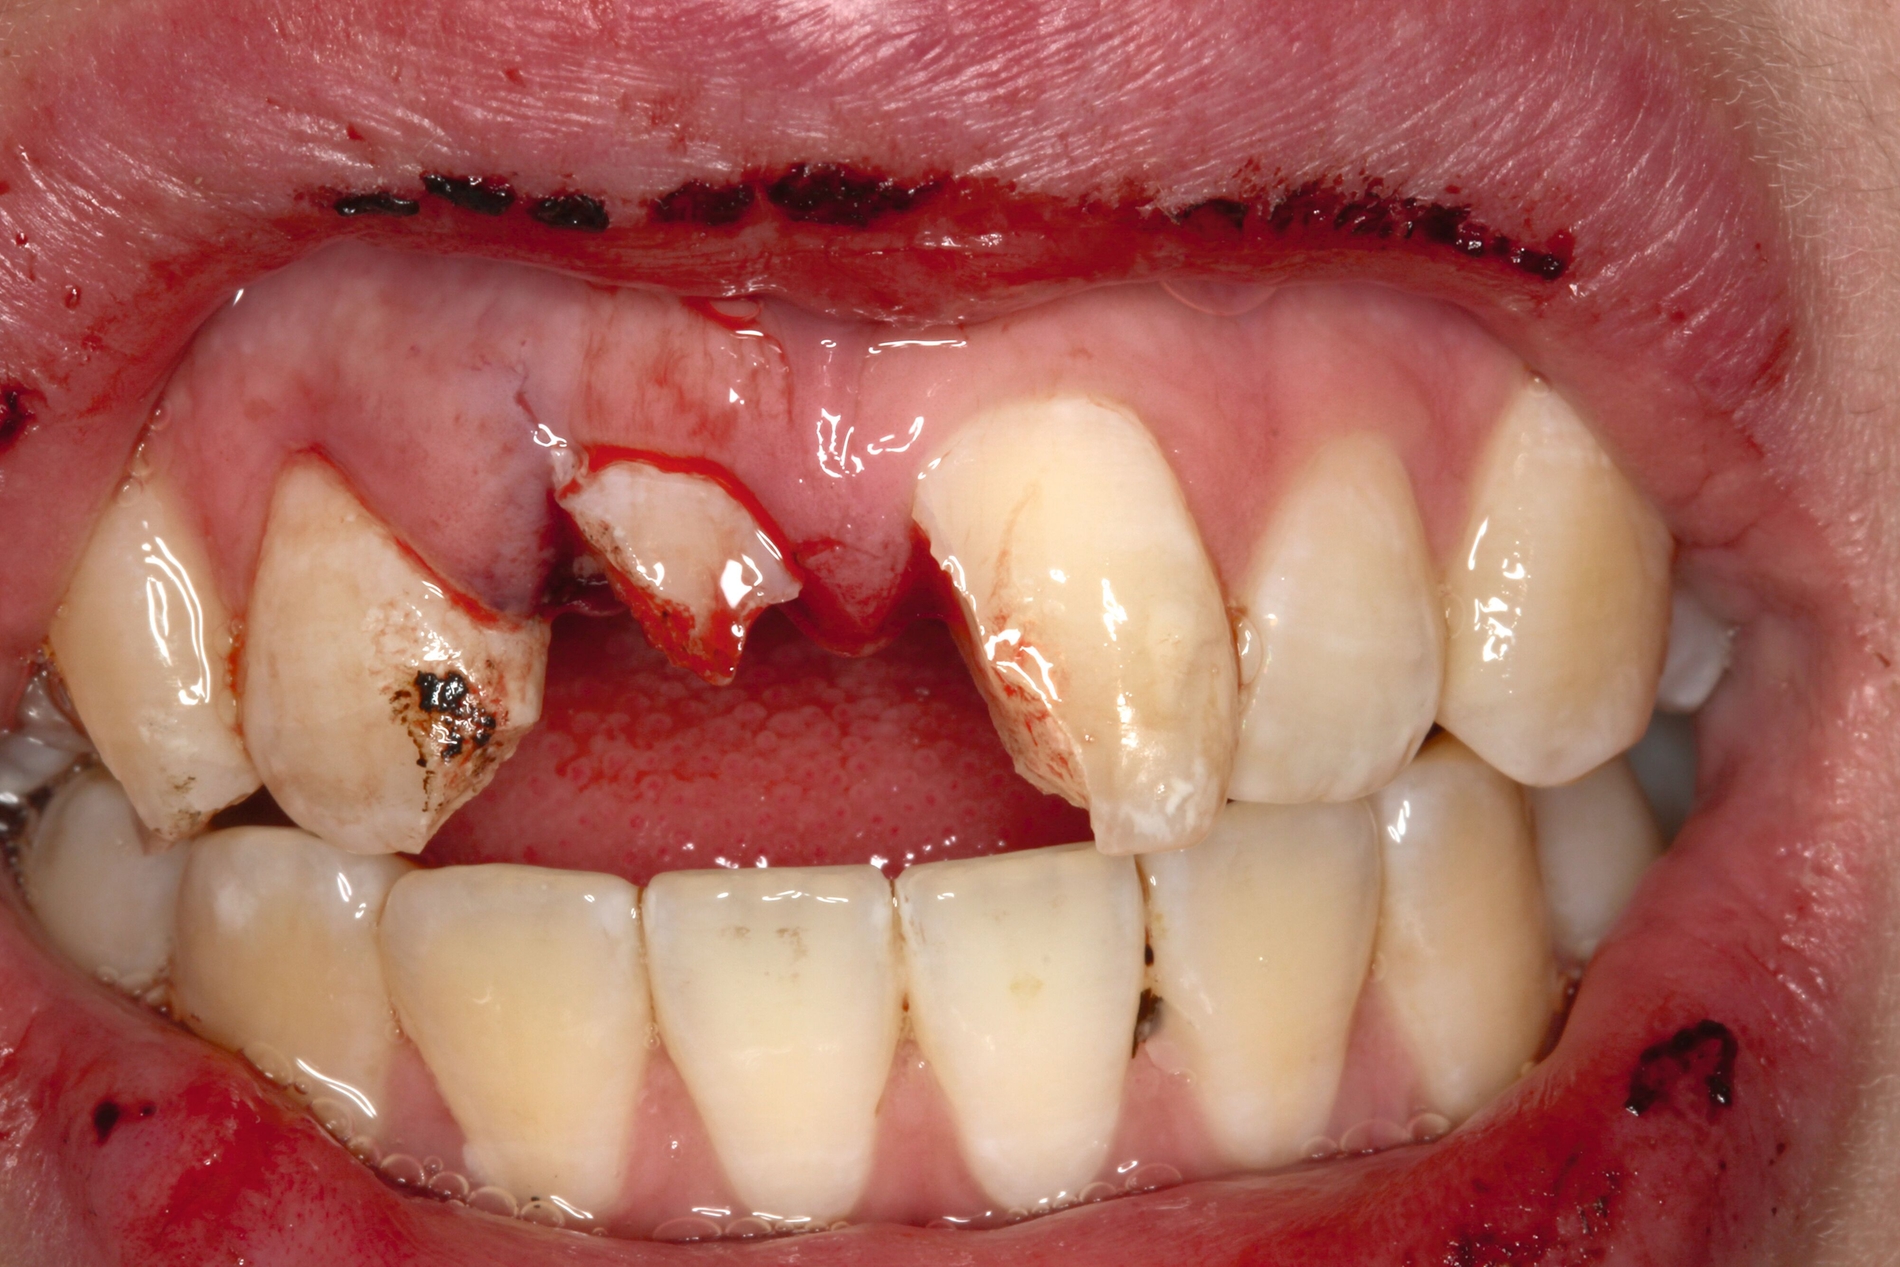

Restaurative Versorgung nach Zahntransplantation oder nach kieferorthopädischem Lückenschluss

Wenn die Lückenversorgung durch eine Transplantation (siehe Teil 4 der Fortbildung „Dentales Trauma“: Chirurgische Aspekte) oder einen kieferorthopädischen Lückenschluss (siehe Teil 5 der Fortbildung „Dentales Trauma“: Kieferorthopädische Aspekte) vorbereitet wurde, beschränkt sich die restaurative Versorgung auf eine Formkorrektur der Zähne. Diese kann – je nach Situation und Präferenz des Behandlers – mit direkten (Abbildung 4) oder mit (minimalinvasiven) indirekten Restaurationen (Veneers, Teilkronen) erfolgen. Gerade bei jungen Patienten muss allerdings berücksichtigt werden, dass im Zuge der passiven Eruption [Mele et al., 2018] Veränderungen des Gingivaverlaufs an den restaurierten Zähnen zur Exposition der Restaurationsränder führen und eine neue Versorgung nach mehreren Jahren erforderlich machen können.